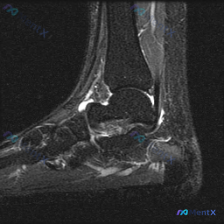

踝关节MRI读片病例分享,整理了完整分析思路 这是一例踝关节矢状位T2加权MRI,我把影像发现和分析思路整理出来,和大家一起讨论。 一、基本影像信息 这是踝关节MRI T2序列矢状位图像,可观察到胫骨远端、距骨、跟骨及周围软组织结构,核心阳性征象如下: 1. 骨骼关节改变:距骨穹窿(圆顶)可见明确局...